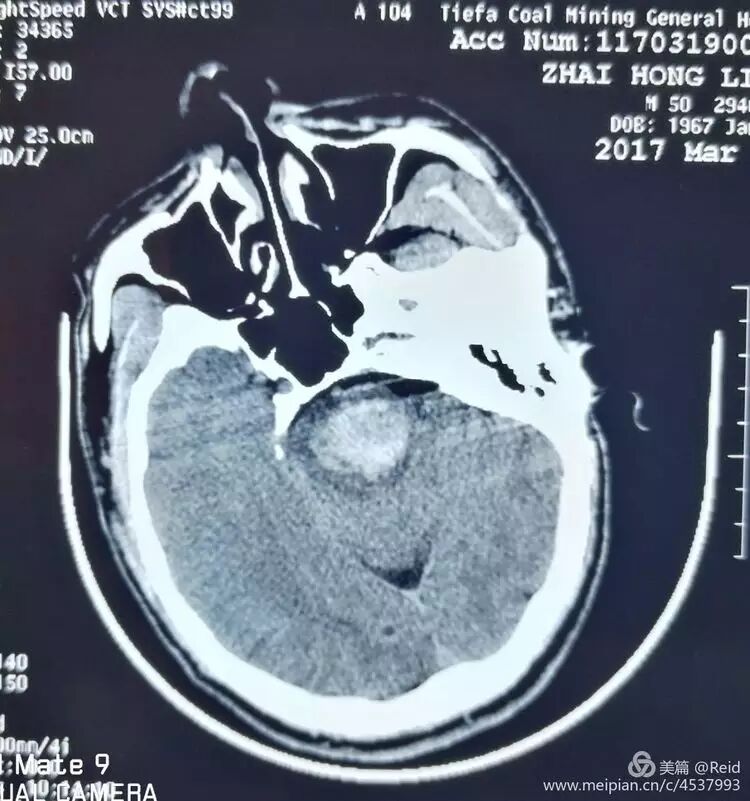

保守治疗72小时后,病情无明显改善,家属决定尝试外科手术干预,谨慎沟通后,以移动呼吸机辅助下,经CT引导精确定位置管手术。

术中将外径3.0mm的细引流管经乙状窦后小脑中脚(脑桥臂)植入桥脑血肿内,术中抽出1-2ml陈旧血肿。术后尿激酶注入融化固体血肿。

术后第5天复查头CT显示桥脑血肿清除满意。